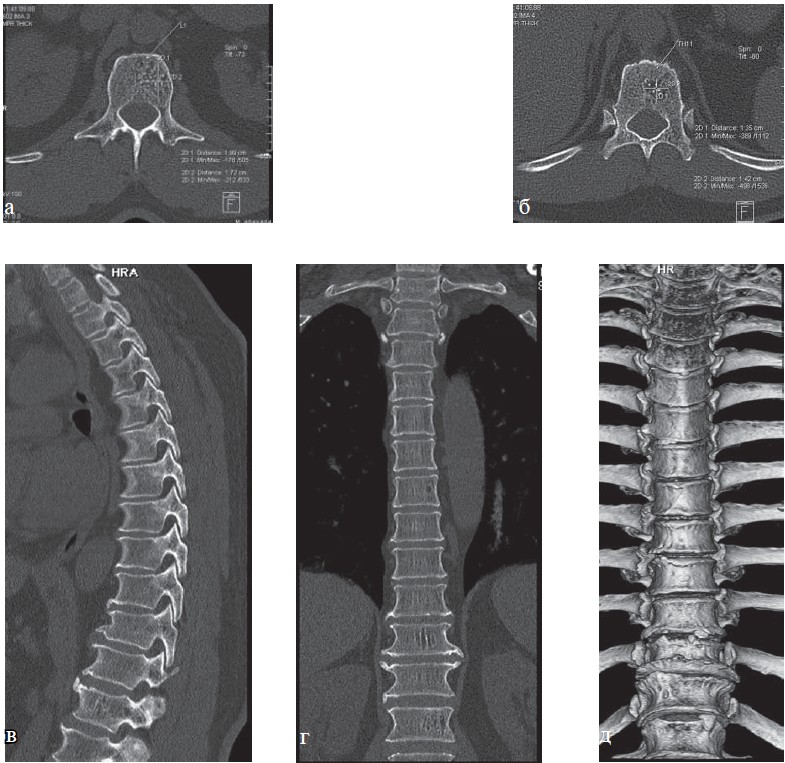

Рис. 9. КТ грудного отдела позвоночника (а—г). Больная С., 63 года. Определяется частичная оссификация передней продольной связки, полная оссификация межостистой связки на уровне грудного отдела позвоночника, костный блок тел позвонков Th4—Th10, костный анкилоз дугоотростчатых суставов Th3—Th12 (проявления болезни Бехтерева), снижение высоты межпозвонковых дисков. Имеются проявления субхондрального склероза замыкательных пластин тел позвонков, обызвествление передней продольной связки, проявления остеоартроза реберно-поперечных суставов, остеоартроза реберно-позвонковых суставов, дугоотростчатых суставов, передний дегенеративный спондилолистез позвонков Th2 и Th3 до 4 мм, S-образный сколиоз грудо-поясничного отдела позвоночника 3 степени.